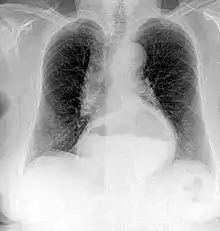

A chest radiograph of a female patient, demonstrating a hiatal hernia

Projectional radiography is the practice of producing two-dimensional images using X-ray radiation. Bones contain a high concentration of calcium, which, due to its relatively high atomic number, absorbs X-rays efficiently. This reduces the amount of X-rays reaching the detector in the shadow of the bones, making them clearly visible on the radiograph. The lungs and trapped gas also show up clearly because of lower absorption compared to tissue, while differences between tissue types are harder to see.

Projectional radiographs are useful in the detection of pathology of the skeletal system as well as for detecting some disease processes in soft tissue. Some notable examples are the very common chest X-ray, which can be used to identify lung diseases such as pneumonia, lung cancer, or pulmonary edema, and the abdominal X-ray, which can detect bowel (or intestinal) obstruction, free air (from visceral perforations), and free fluid (in ascites). X-rays may also be used to detect pathology such as gallstones (which are rarely radiopaque) or kidney stones which are often (but not always) visible. Traditional plain X-rays are less useful in the imaging of soft tissues such as the brain or muscle. One area where projectional radiographs are used extensively is in evaluating how an orthopedic implant, such as a knee, hip or shoulder replacement, is situated in the body with respect to the surrounding bone. This can be assessed in two dimensions from plain radiographs, or it can be assessed in three dimensions if a technique called '2D to 3D registration' is used. This technique purportedly negates projection errors associated with evaluating implant position from plain radiographs.[101]